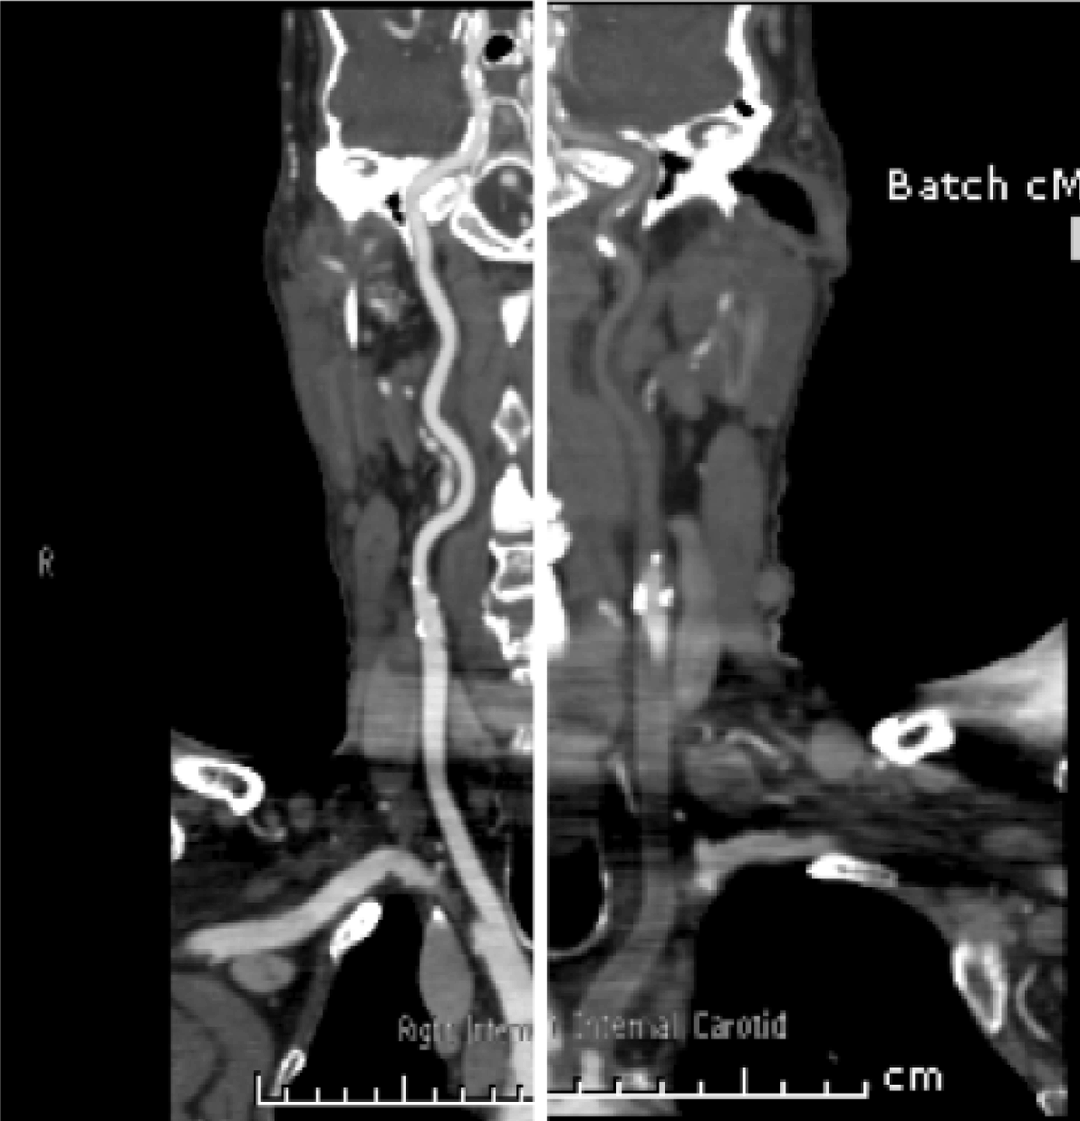

A 73-year-old male with metastatic sarcomatoid carcinoma underwent a restaging computed tomography (CT) scan that incidentally identified complete occlusion of the left common carotid at its origin and narrowing of the origin of the right brachiocephalic artery. (Figure 1) Mucosal thickening was noted with dissection through the mucosa and atheromatous plaques in the aortic arch with a pedunculated 1.9 cm thrombus. (Figure 2 A–B) The lesion was suspicious for metastasis.

Figure 2: Pedunculated thrombus of the aortic arch (A) Sagittal view, (B) Coronal view.